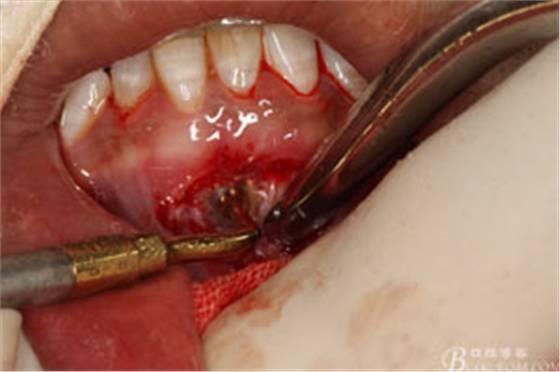

圖7.局部麻醉下,行下前牙唇側(cè)弧形切口,翻瓣可見31唇側(cè)骨壁有缺損,并有根充物暴露